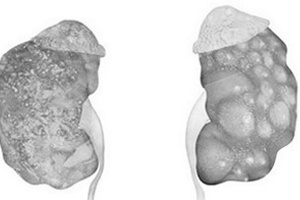

Абсцессом называют очаг нагноения внутри ткани органа или участка тела, он может быть микроскопическим или макроскопическим. Большинство абсцессов — это острые заболевания, однако в ряде случаев встречаются и хронические. Почечные абсцессы расположены в пределах почечной паренхимы, тогда как абсцессы около почечной клетчатки ограничены периренальной фасцией — фасцией Героты.

Почечные абсцессы — это локализованные поражения почек, которые располагаются интрапаренхиматозно (кортикальная, медуллярная или инфицированная почечная киста) или ограничены в пределах чашечки при ее обструкции. Периренальные абсцессы располагаются в периренальном пространстве, ограниченном околопочечной фасцией Героты. В большинстве случаев периренальные абсцессы связаны с почечными абсцессами.

При почечном абсцессе наблюдается острое начало заболевания. Типичными признаками при этом состоянии являются озноб, лихорадка, боль и болезненность при пальпации в костовертебральном углу. В тех случаях, когда возникновение заболевания обусловлено инфекционным процессом, поражающим нижние мочевыводящие пути, наблюдаются также учащенное мочеиспускание, позывы на мочеиспускание и дизурия. Могут отмечаться тошнота и рвота, которые часто приводят к тому, что врач подозревает наличие заболевания органов брюшной полости. Симптоматика при паранефральном абсцессе обычно неотчетливая. Как правило, у больных сложная клиническая картина, а симптомы заболевания появляются за несколько недель до обращения к врачу. Часто пациентов беспокоят лихорадка и недомогание. В большинстве случаев при почечном и около почечном абсцессах поражение одностороннее. При физикальном обследовании определяется болезненность в боку и в костовертебральном углу. Сколиоз с наклоном в сторону поражения является типичным проявлением. При большом почечном абсцессе или при около почечном абсцессе можно выявить объемное образование в боку или в проекции живота и отек кожи в поясничной области. Распространение процесса на бедро приводит к усилению болей за счет натяжения поясничной мышцы.

Обзорная урограмма часто позволяет выявить наличие объемного образования и сколиоз с наклоном в сторону поражения. Размеры почек могут быть увеличены, и, если воспаление выходит за пределы почки, определяется сглаженность контуров поясничных мышц. На основании результатов внутривенной урографии можно заподозрить наличие этой патологии, однако основную информацию о наличии абсцесса забрюшинного пространства дают ультразвуковое исследование и, особенно, компьютерная томография (КТ). Они позволяют оценить локализацию, размер и протяженность абсцесса. КТ более информативна, чем ультразвуковое исследование, ее следует выполнять каждому больному с подозрением на ретроперитонеальный абсцесс. Почечная артериография и радионуклидные исследования в диагностике применяются редко.